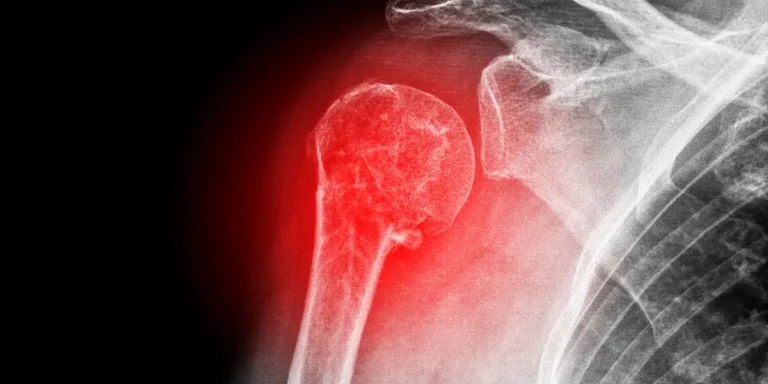

A definição do tratamento ideal envolve avaliação técnica detalhada. Especialistas consideram três elementos-chave: grau de deslocamento ósseo, quantidade de partes quebradas e características individuais do paciente.

Quando indicar a intervenção cirúrgica

Deslocamentos superiores a 1 cm geralmente exigem correção cirúrgica. Esse limite garante a reconstrução adequada da anatomia articular. Lesões com mais de três fragmentos aumentam a complexidade, necessitando fixação interna precisa.

Pacientes jovens com alta demanda física recebem prioridade para procedimentos. Já idosos com ossos porosos podem precisar de técnicas adaptadas, como próteses articulares. Cada situação requer análise personalizada.

O papel do ortopedista e dos exames complementares

O ortopedista especialista cruza dados clínicos com exames de imagem avançados. Tomografias revelam detalhes invisíveis em radiografias comuns, permitindo mapear fragmentos milimétricos.